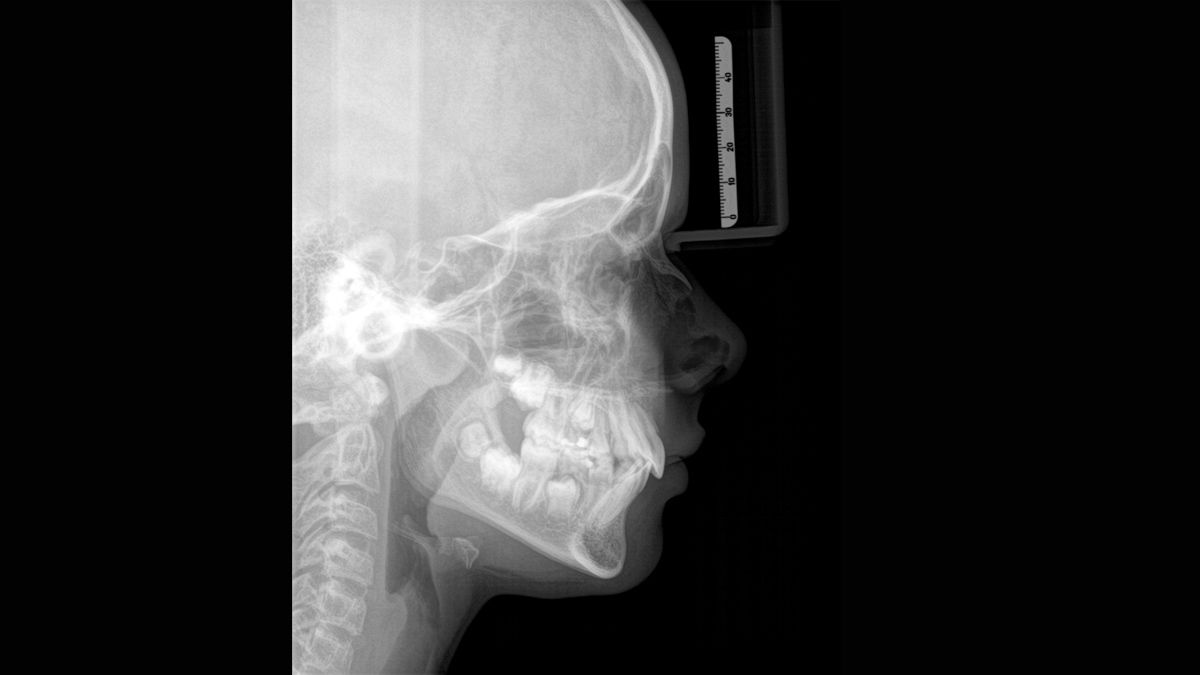

Algoritmo de software ASTRA

ASTRA mejora considerablemente la calidad de las imágenes panorámicas 2D y cefalométricas. Este algoritmo de reconstrucción estructurado anatómicamente genera una imagen con mayores contrastes sin la aparición de bordes indefinidos.